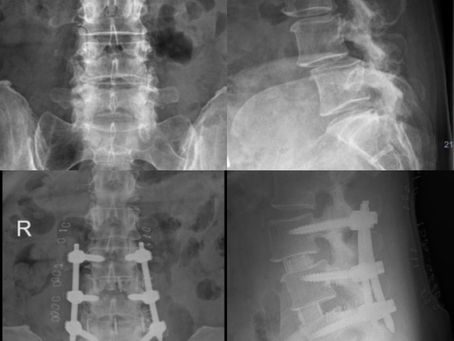

Isthmic L5/S1 Spondylolisthesis

53 year old lady presented with bilateral leg and back pain. X-ray and MRI showed grade II spondylolisthesis and severe bilateral...

Sureisen Mariapan

Apr 29, 20201 min read